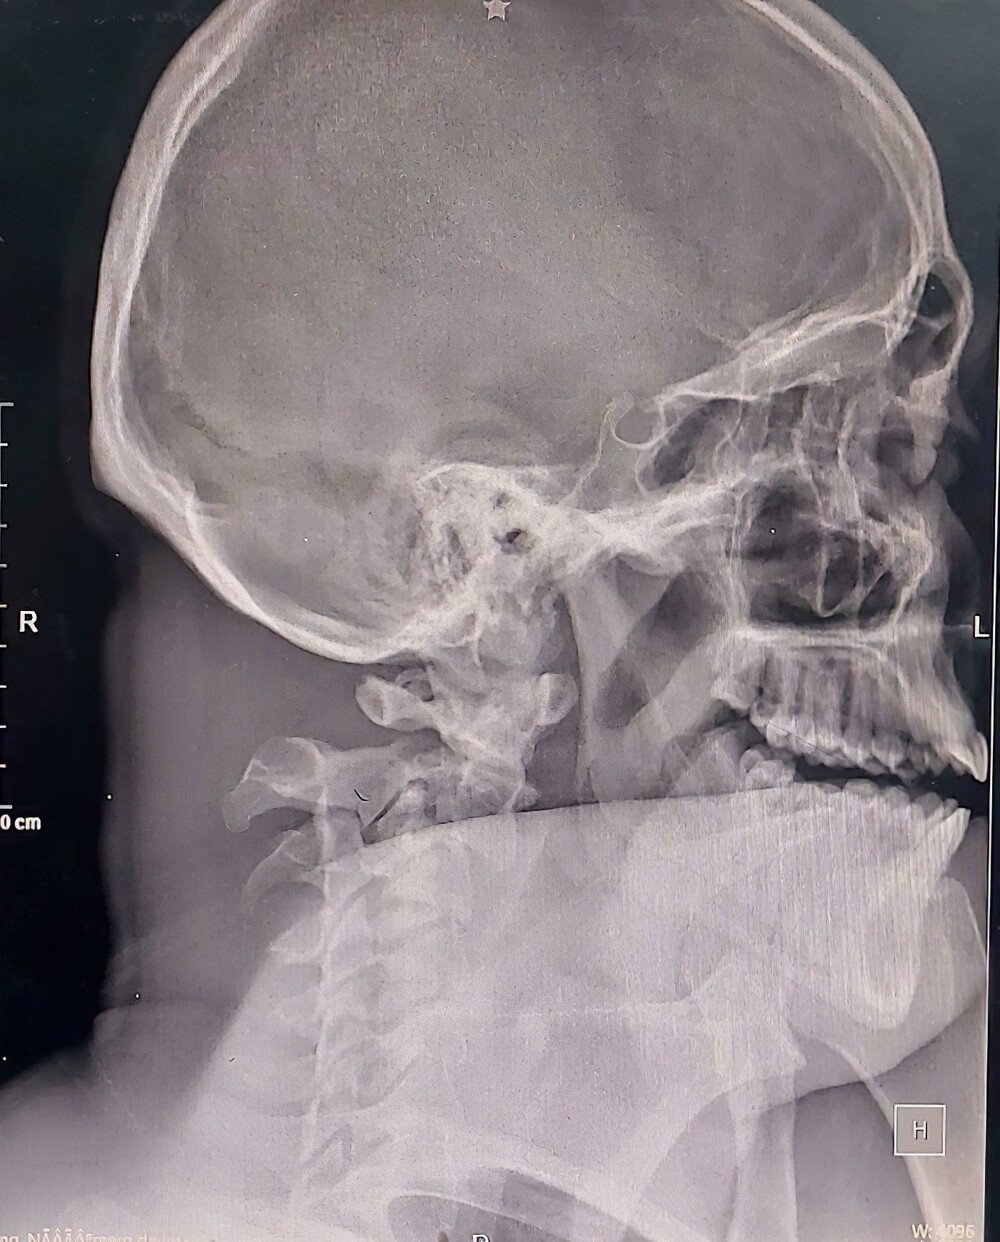

20. A man with a fracture of the cervical spine somehow managed to come to the intensive care unit on his own, by taxi